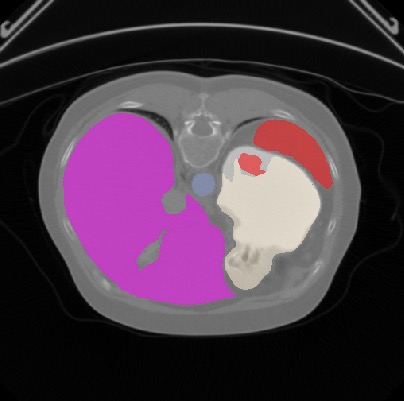

Transformers, the default model of choices in natural language processing, have drawn scant attention from the medical imaging community. Given the ability to exploit long-term dependencies, transformers are promising to help atypical convolutional neural networks (convnets) to overcome its inherent shortcomings of spatial inductive bias. However, most of recently proposed transformer-based segmentation approaches simply treated transformers as assisted modules to help encode global context into convolutional representations without investigating how to optimally combine self-attention (i.e., the core of transformers) with convolution. To address this issue, in this paper, we introduce nnFormer (i.e., Not-aNother transFormer), a powerful segmentation model with an interleaved architecture based on empirical combination of self-attention and convolution. In practice, nnFormer learns volumetric representations from 3D local volumes. Compared to the naive voxel-level self-attention implementation, such volume-based operations help to reduce the computational complexity by approximate 98% and 99.5% on Synapse and ACDC datasets, respectively. In comparison to prior-art network configurations, nnFormer achieves tremendous improvements over previous transformer-based methods on two commonly used datasets Synapse and ACDC. For instance, nnFormer outperforms Swin-UNet by over 7 percents on Synapse. Even when compared to nnUNet, currently the best performing fully-convolutional medical segmentation network, nnFormer still provides slightly better performance on Synapse and ACDC.